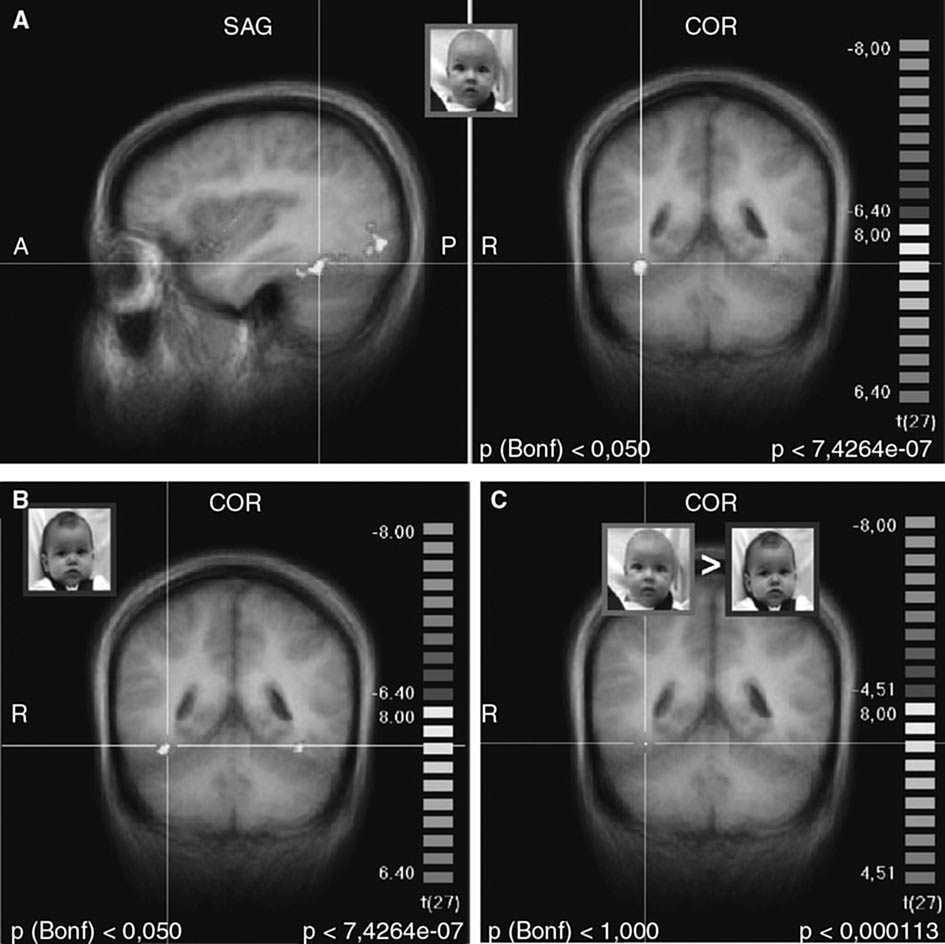

Respuestas cerebrales maternasAntes de abordar las hipótesis específicas de este estudio, examinamos las respuestas cerebrales maternas a las caras de niños con estado neutro, comparado con la ausencia inicial de caras. Como se esperaba, los estímulos de la cara activaron las regiones cerebrales a lo largo de la vía visual ventral entre la corteza visual primaria y el lóbulo temporal, incluyendo la circunvolución fusiforme y la denominada “área fusiforme de la cara” (figs. 2A y 2B)50. Sin embargo, al contrastar las caras del niño “propio” y “desconocido” (ON > UN) no persistió una activación significativa, ni siquiera a menores umbrales estadísticos (fig. 2C). Así pues, no hubo diferencias significativas en la respuesta de la vía visual posterior entre los estímulos faciales de la cara del hijo y la del niño desconocido.

Fig. 2. Activación de la vía visual ventral, incluyendo el área fusiforme facial (coordenadas de Talairach 36, –46, –17) por las caras de hijo/neutro y de lactante desconocido/neutro. A. Imágenes coronal y transversal de la activación por la cara del hijo/neutro (ON), comparado con la situación inicial sin cara. B. Imagen coronal de la activación por la cara de un lactantedesconocido/neutro (UN), comparado con la situación inicial sin cara. C. Contraste entre ON > UN, que no muestra activación residual de la vía visual o del área fusiforme facial. (A y B: p < 0,000001, corrección de Bonferroni p < 0,05, C: p < 0,0001, no corregido; umbral de agrupación 100 m3). A: anterior; COR: coronal; D: derecha; P: posterior; SAG: sagital.